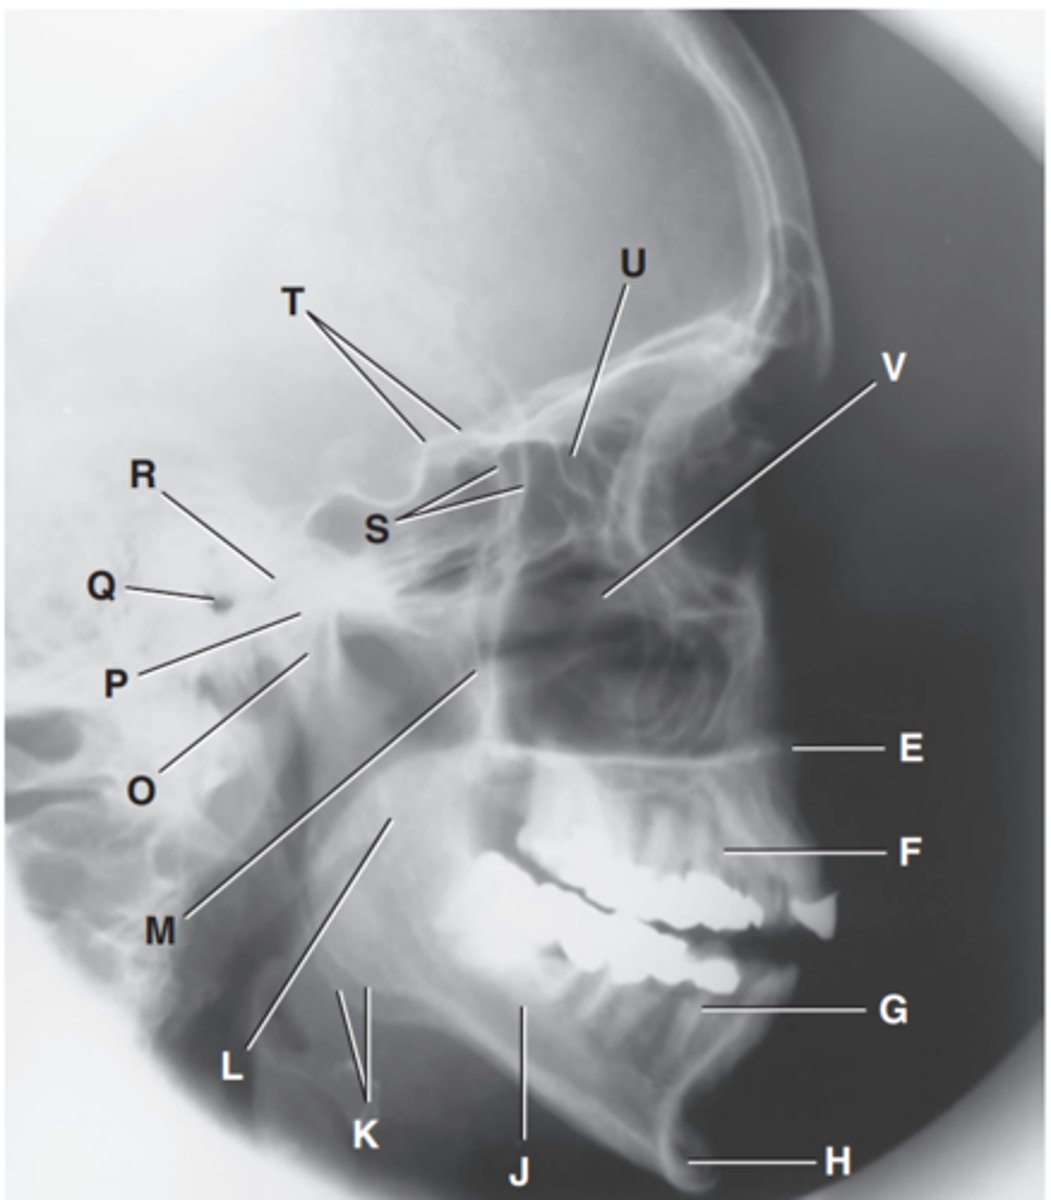

Zygomatic arch

Label A

Right zygomatic bone

Label B

Right nasal bone

Label C

Frontal process of right maxilla

Label D

Anterior nasal spine

Label E

Alveolar process of maxilla

Label F

Alveolar process of mandible

Label G

Mentum or mental protuberance

Label H

Mental foramen

Label I

Body of mandible

Label J

Angle (gonion)

Label K

Ramus of mandible

Label L

Coronoid process

Label M

Mandibular notch

Label N

Neck of mandibular condyle

Label o

Condyle or head of mandible

Label P

EAM

Label Q

TM fossa of temporal bone

Label R

Greater wings of sphenoid

Label S

Lesser wings of sphenoid with anterior clinoid processes

Label T

Ethmoid sinuses between orbits

Label U

Body of maxilla containing maxillary sunuses

Label V